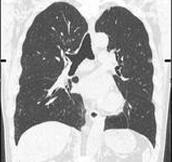

Lung area analysis software 3D display and automatic volume calculation for nodules.